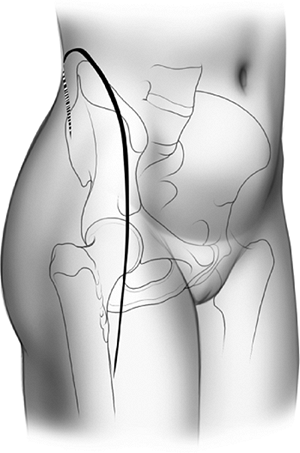

and begins at the posterior–superior iliac spine, extending along the

iliac crest toward the anterior–superior iliac spine (ASIS). From here,

the distal arm of the incision proceeds along the anterolateral aspect

of the thigh for a distance of 15 to 20 cm (Fig. 43.8).

The surgeon has a tendency to make this arm more medial than is

desired. To avoid this, one should visualize a point 2 cm lateral to

the superolateral pole of the patella. With the leg held in neutral

rotation, this location is generally in line with the desired incision.

Furthermore, a gentle posterior curve may be helpful in obese patients.